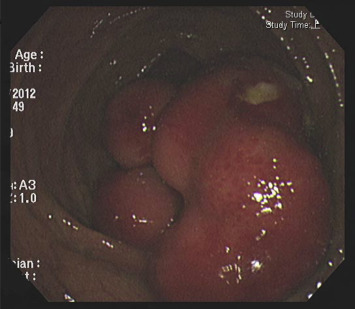

A 50-year-old man without a personal or family history of colorectal cancer presented with a 5-month history of loose yellow-colored stool passage and intermittent periumbilical pain. Recently, the stool consistency had become mucus-tinged and bloody, occurring approximately twice a day, and accompanied by upper abdominal pain. When he visited our clinic, we performed a colonoscopy and found a large, sessile, hard polypoid mass with congestive overlying mucosa and focal ulcerations involving the ileocecal valve and ascending colon (Figure 1 ). The colonoscope could not be inserted into the terminal ileum because the orifice of the ileocecal valve was almost completely obstructed by the tumor.

A large, sessile, hard polypoid tumor with a congestive overlying mucosa and ...

Figure 1.

A large, sessile, hard polypoid tumor with a congestive overlying mucosa and focal ulcerations involving the ileocecal valve and ascending colon.

Colonoscopic findings may provide direct inspection of submucosal lipoma with endoscopic features, including the “tenting sign”, “cushion sign”, and “naked fat sign”. In our patient, however, the large size of the polypoid lipoma precluded evaluation of the “tenting sign” and “cushion sign”.